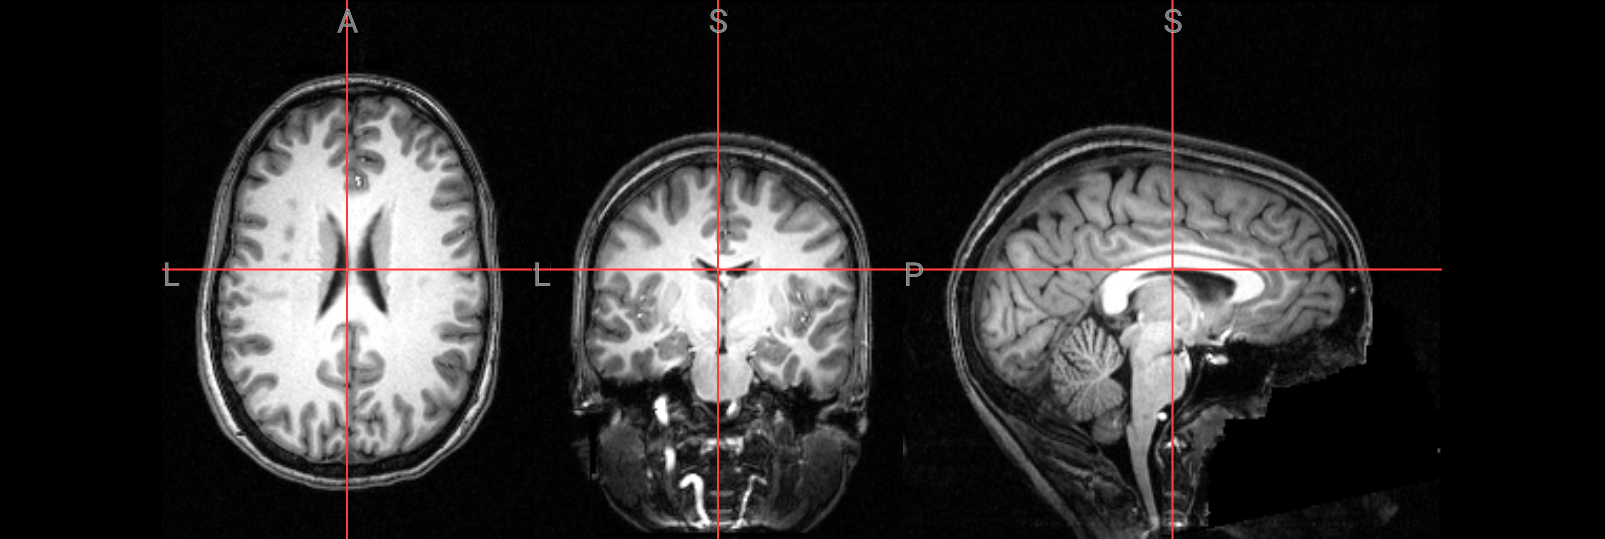

Inspecting the anatomical and functional images#

Before beginning any preprocessing or analysis, it’s essential to visually inspect both anatomical and functional MRI data. This helps catch common issues such as motion artifacts, abnormal intensities, or poor image quality that could affect downstream results. To look at the data with FSL’s image viewer, you would type:

We will use NiiVue to look at the data:

# anatomical image

nv = NiiVue()

nv.load_volumes([{"path": "./ds000102/sub-08/anat/sub-08_T1w.nii.gz"}])

nv

Image(url='https://raw.githubusercontent.com/NeuroDesk/example-notebooks/refs/heads/main/books/images/fsl_preproc_anat.png')